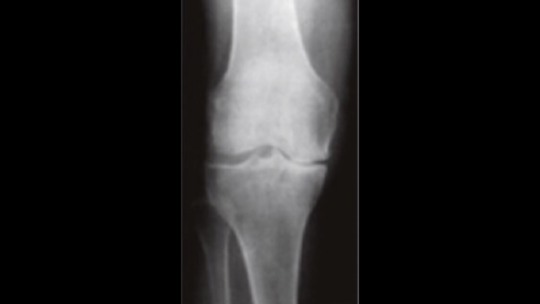

病院でレントゲン・CT・MRIを撮って、『膝関節の変形がある。手術しか方法はない!』と医師から言われることがよくあります。

変形性膝関節症の完治は手術しなくてはいけないが、手術前の可動域が術後の可動域の目安になる事はあまり知らない事なので膝関節で悩まれている方は知っておいた方がいい情報になります。